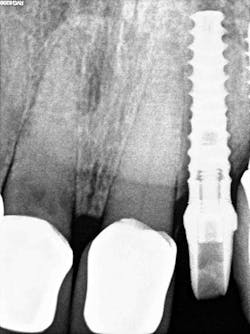

Case report: Extraction/immediate implant placement with provisional, using the Ditron Ultimate Implant System

- Radiographic findings: Fractured lateral incisor with periapical pathology

- Implant: Ditron Ultimate 3.75 x 16 mm

- Abutment: Final straight 11.5 mm titanium abutment delivered at time of implant placement

Conclusion

The patient related to our office that he had absolutely no postoperative discomfort, no prosthesis complications, and was very impressed by the entire experience as he had a different outcome for his previous implant tooth replacements.Disclosures or conflicts of interest: Dr. Miller has a financial relationship with Ditron Dental USA. Products mentioned are used in the regular course of practice.